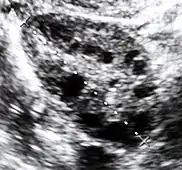

| Diagnostic method | Blood tests, ultrasound[1][4] |

Polycystic ovary syndrome accounts for about 70% of hyperandrogenism cases.[1] Other causes include adrenal hyperplasia, insulin resistance, hyperprolactinemia, Cushing's disease, certain types of cancers, and certain medications.[4][1][3] Diagnosis often involves blood tests for testosterone, 17-hydroxyprogesterone, and prolactin, as well as a pelvic ultrasound.[1][4]